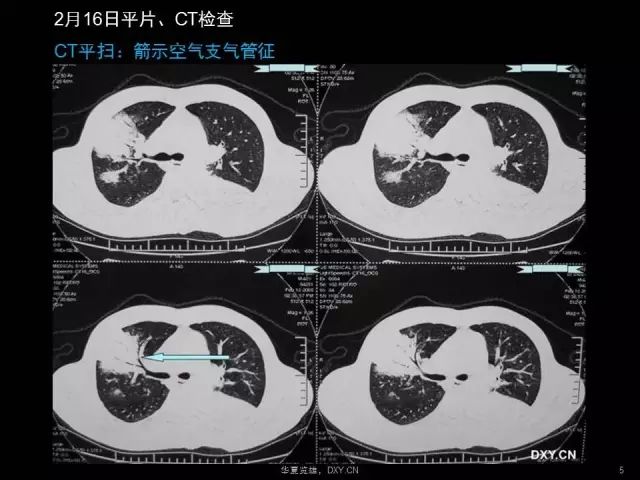

肺炎、肺癌、肺结核在影像学上的征象往往千变万化。